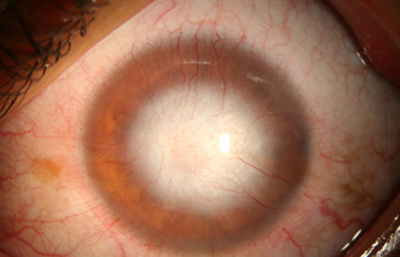

Superficie corneal irregular y grisácea, (Fig. 1, 2) con opácidades granulares en parche y formación de líneas epiteliales elevadas de aspecto granular (Fig. 3), que pueden arborizar dando imágenes de pseudodendritas. Opacidades superficiales satélites. (Figura 4) Inyección ciliar. Ulceración epitelial variante. (Figura 5).

Fig. 4 Focos satélites. Síntomas de meses evolución.